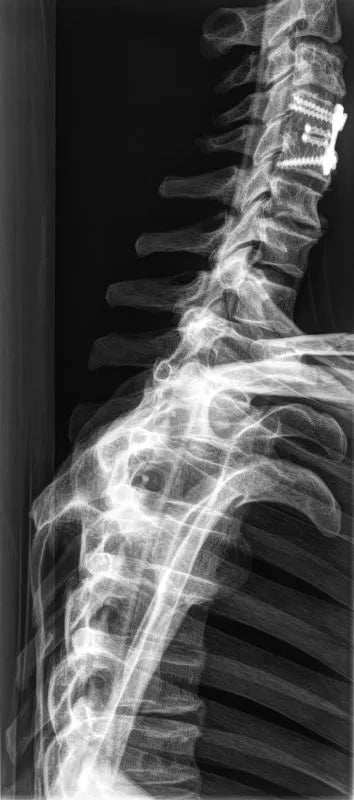

The whole-body X-ray phantom serves for practical training in projection radiography as well as in positioning and positioning techniques. It enables the production of realistic X-ray images under training conditions and depicts anatomical structures in their natural size.

The phantom contains a natural human skeleton. Additionally, the outlines of the larynx, lungs, heart, and kidneys are integrated, appearing as shadows on the X-ray images. This allows for the creation of images that accurately reflect the conditions found in patients. The use of a real skeleton enables the identification of bony landmarks that are not visible in plastic models.

The joints are mounted with full mobility, allowing positioning in common radiological standard positions, including special positions such as the frog position and pronation and supination of the forearm. The arms can be raised, so the phantom can also be used for bone examinations in CT scans. Particular attention was paid during assembly to the realistic representation of the joint spaces.

Each phantom is a handcrafted, unique piece. Variations in size, design, and appearance are possible. Depending on the model, pathological findings may be present. The revised design was developed in collaboration with a German training institution for medical-technical radiology assistants and meets the requirements of modern training concepts.